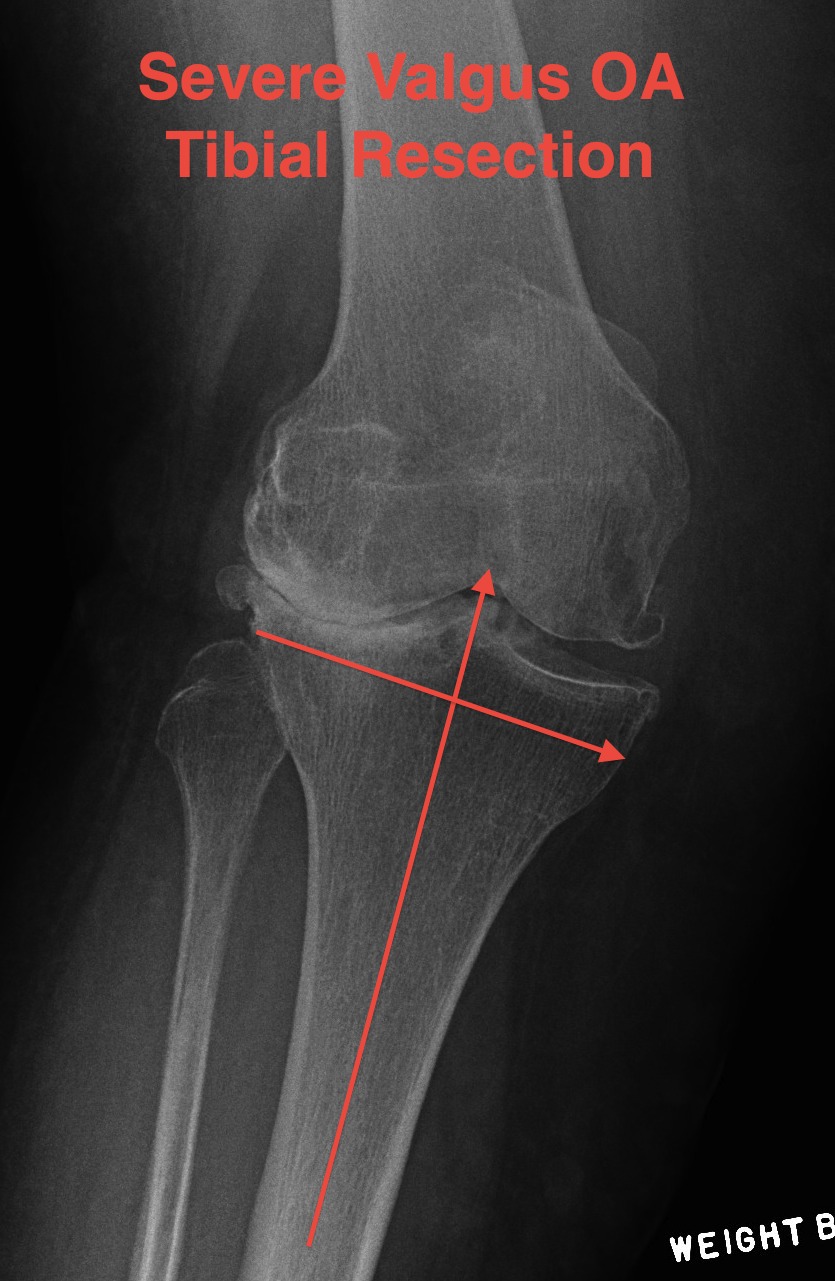

Tibial resection

- don't take 10 mm as bone worn laterally in valgus OA

- can't take 2mm off medial side as is the normal side

- need to estimate

- take 6 mm from lateral tibia intially, stay above fibula head

- much more symmetric proximal tibial resection

- use trial blocks to assess flexion / extension gaps

TKR Valgus OA Tibial Resection

Deficient lateral tibial plateau

- don't take > 10 mm medial plateau

- will get down into soft bone

- preop plan

- may need augments laterally and therefore stems

- below xray is borderline / but just ok

TKR Severe Valgus Tibial Resection Planning